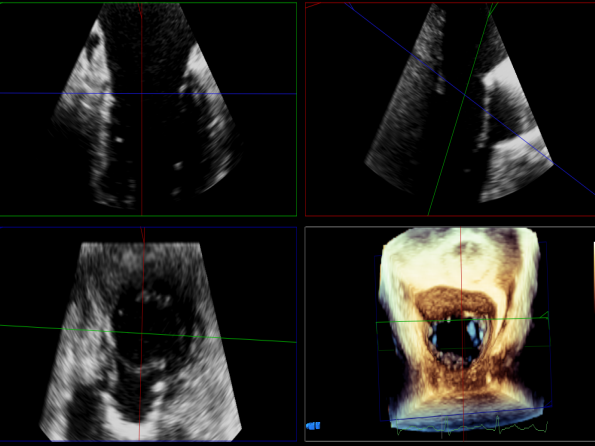

过大鞘

出夹子,做trajactory

调rotate

夹子进左室

瓣叶捕获后,前叶抓捕长度9.1mm,后叶抓捕长度7.8mm

外侧残余少量分流

第一个夹子外侧残余小脱垂

残余分流主要来源于残余脱垂区域

评估瓣口条件,平均跨瓣压差:2mmHg,决定在第一个夹子外侧下第二个夹子

第一个夹子外侧放第二个夹子

第二个夹子捕获瓣叶后,前叶抓捕长度9.3mm,后叶抓捕长度7.3mm

未见明确残余分流

三维评估两个夹子位置

3D-color再次确定未见残余分流

评估瓣口条件,平均跨瓣压差:4mmHg

肺静脉血流频谱恢复正常